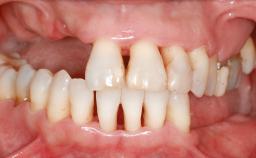

A 20-year-old woman was referred for implant therapy in 2004. Her medical history revealed no significant findings, and neither did she smoke nor take any medications. An extraoral examination revealed no abnormalities of the skin, hair or nails. The intraoral examination revealed only 11 permanent teeth clinically. These were normal in shape, size, and color. In addition, eight retained deciduous teeth (53, 62, 63, 71, 72, 73, 81, 82) were present. No abnormalities were detected during the general examination. The family history revealed that the patient’s father and two sisters were on record with similar conditions. The clinical examination revealed a thick gingival biotype. No recession of the attached gingiva was noted, but the retained deciduous teeth were mobile and unsightly. As a syndrome had not been diagnosed, the case was categorized as non-syndromic oligodontia.